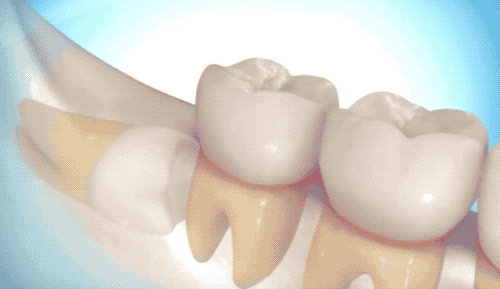

首先介紹相對(duì)簡(jiǎn)單的拔除,雖然沒(méi)有完全長(zhǎng)出來(lái),但是沒(méi)有長(zhǎng)歪的那類智齒。

切開(kāi)牙床,翻開(kāi)牙肉,露出白白的牙槽骨和智齒。很多人白的牙齒可能就是沒(méi)有完全萌發(fā)的智齒了…

看到里頭白白的,豎著長(zhǎng)還挺乖的智齒,用牙挺直接撬出來(lái)即可。有時(shí)候醫(yī)生也會(huì)拿錘子敲一敲,用鉗子給揪下來(lái)。